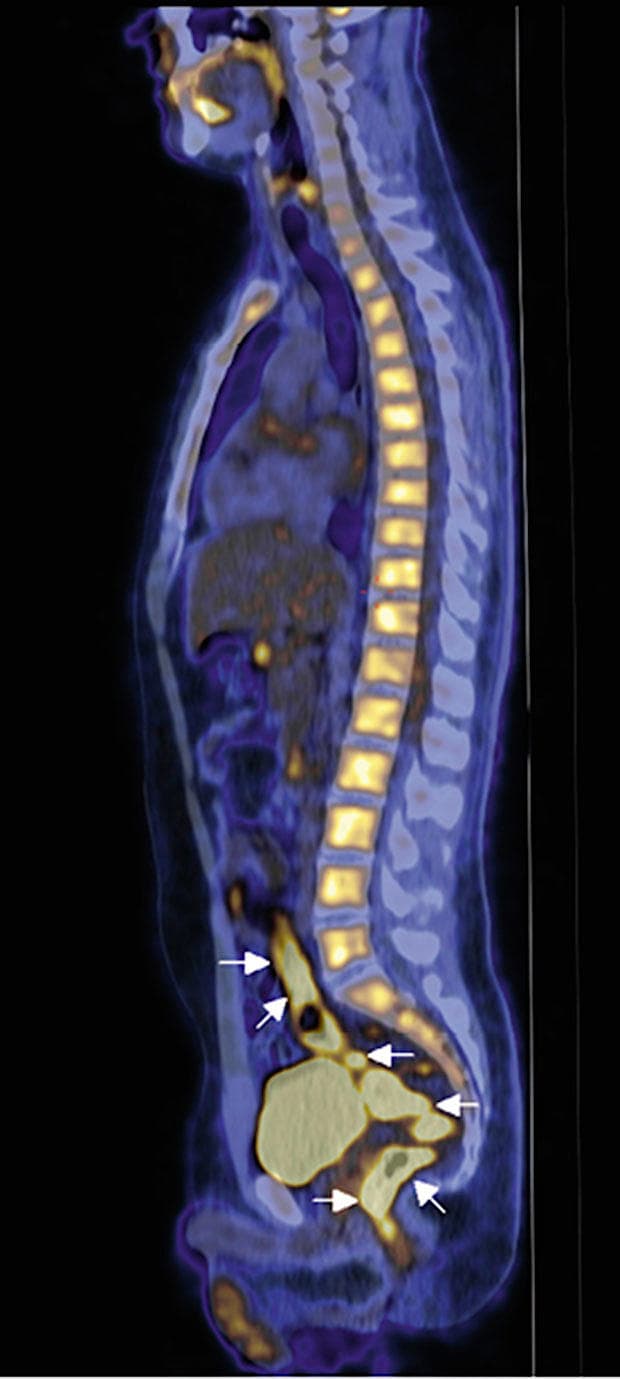

Da han nu igen havde haft intermitterende feber gennem måneder uden erkendt årsag, blev han henvist til PET/CT. På PET/CT’en ses kraftigt øget fluordeoxyglukose (FDG)-optagelse og dermed metabolisme i den terminale colon sigmoideum, rectum og analkanalen, med fortykket tarmvæg og skip lesions på lavdosis-CT, hvilket er foreneligt med mb. Crohn [1].